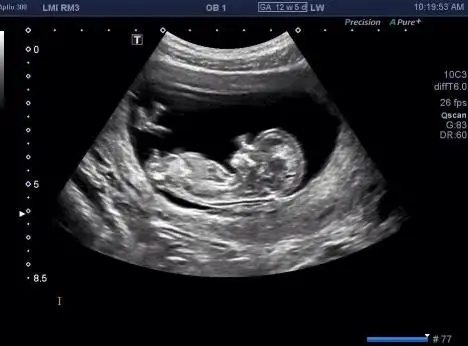

Aaaaaa cidden dimdik nasil belli nub u..sana supriz yapmasin bebek doguncaBen nubu gördüm doktor bakarken, aynı bu şekildeydi. Doktor da nubun açısı dik, %80 erkek dedi.

Cok net bisekilde belli Nub dimdik duruyor. Allahim hayirla kucagina almak nasip etsin insallah. Benimde 12. haftada bikac usg foto var fakat kesinlikle nub gözükmüyor..Bana da 12' in içinde erkeğe benziyor dendi. Ben nubu gördüm doktor bakarken, aynı bu şekildeydi. Doktor da nubun açısı dik olduğu için %80 erkek dedi.

Ha bu nub, birden bire paralele dönüşürse o da Allahın takdiridir zaten kız erkek önemli değil, sağıklı olsun da.

Bana da 12' in içinde erkeğe benziyor dendi. Ben nubu gördüm doktor bakarken, aynı bu şekildeydi. Doktor da nubun açısı dik olduğu için %80 erkek dedi.